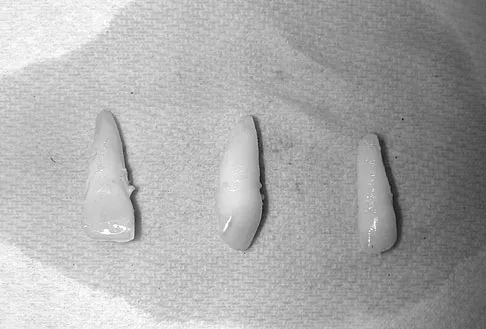

Question 33 High Yield

A 15-year-old female field hockey player sustains a blow to the mouth from a hockey stick. Three front teeth are knocked out and shown in Figure 4. In addition to calling a dentist immediately, what is the next best step in management?

Detailed Explanation